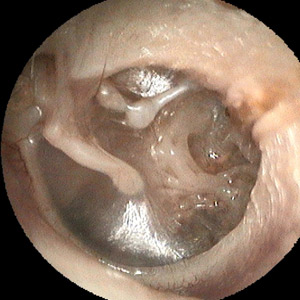

Adhäsivprozess

Permanente Belüftungsprobleme im Mittelohr können zu einer starken Einziehung des Trommelfells führen, so dass in ausgeprägten Fällen das Trommelfell wie eine Tapete auf der gegenüberliegenden Wand des Mittelohrs zu liegen kommt und das sonst luftgefüllte Mittelohr kaum noch Luft enthält. Man spricht dann vom Mittelohradhäsivprozess oder der chronischen Otitis media adhäsiva.